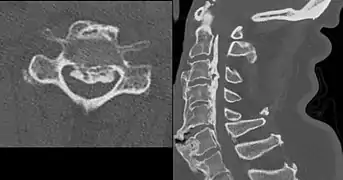

Ectopic calcification and new bone formation in diffuse idiopathic skeletal hyperostosis (DISH)

Ossification of the posterior longitudinal ligament in DISH